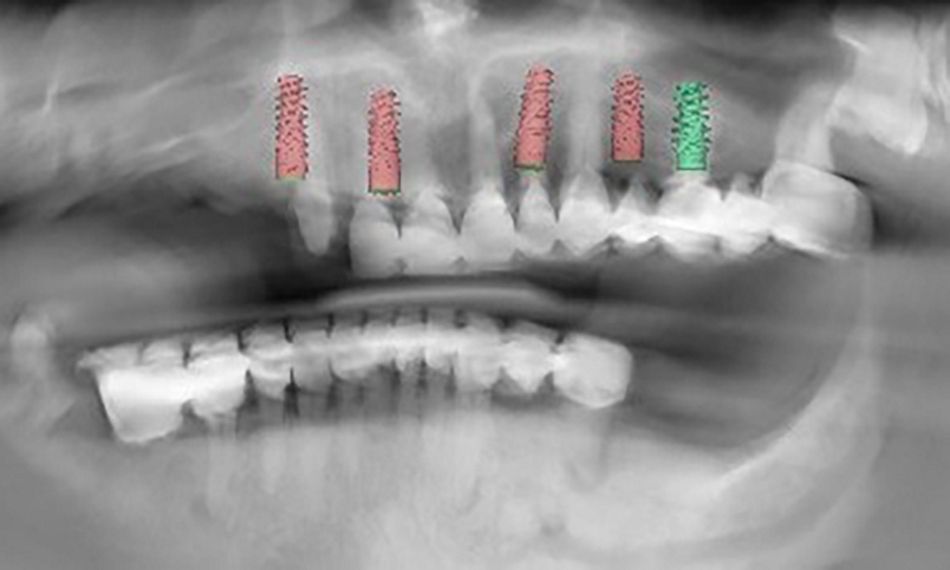

The radiographic examination showed images compatible with periapical infections at several upper roots (Fig. 5).

1. Clinical and radiographic assessments and digital implant planning. The implant planning process was carried out meticulously, utilizing digital models created by combining Cone Beam Computed Tomography (CBCT) and intraoral scans. The approach taken was prosthetically driven, with the aim of achieving an ideal positioning for the dental implants. The advanced coDiagnostiX® surgical planning software and 3shape smile composer facilitated this integration. The synergy of these technologies allowed for a comprehensive and detailed approach to implant planning, ensuring precision and accuracy in the overall treatment strategy (Figs 6-9).